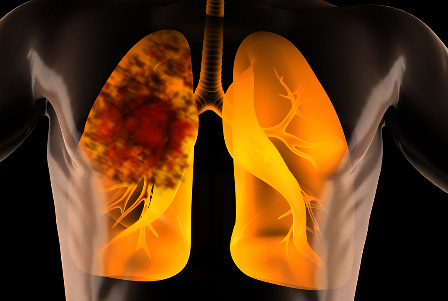

폐암이란

폐암이란 우리 몸의 폐에 생긴 악성 종양을 말합니다. 원발상 폐암이라고 해서 폐 자체에서 발생하거나 다른 장기에서 생긴 암이 폐로 전이될 수도 있습니다. 원발성 폐암의 종류에는 암세포의 형태와 크기에 따라 비소세포 폐암과 소세포 폐암으로 구분합니다. 폐암의 80~85%는 비소세포폐암에 해당하며 이것은 다시 선암(샘암), 대세포암, 편평상피세포암 등으로 나뉩니다. 그리고 소세포폐암은 대체로 악성도가 높아 발견되었을 때 이미 림프관 또는 혈관을 통하여 다른 장기나 반대편 폐, 종격동, 기관, 식도, 대동맥, 양쪽 폐 사이의 공간으로 심장 등으로 전이되어 있는 경우가 많습니다.